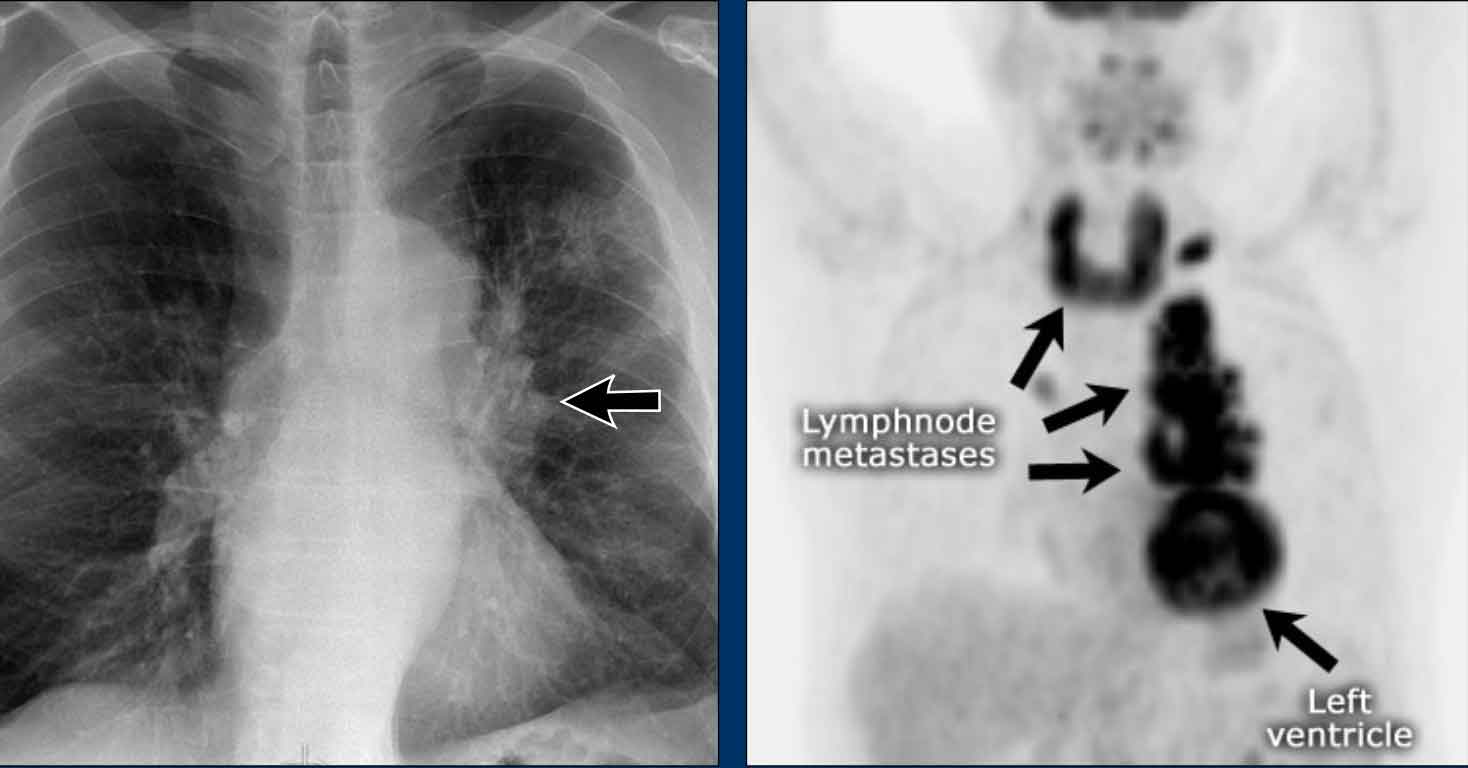

AP window pathology - case 1

Imaging

• PA film shows a mass filling the aortopulmonary window

• Lateral view shows no enlarged pulmonary vessels (black arrow), but a mass projecting into the retrosternal space (white arrow)

Continue with the CT...

CT Imaging

• Mass in the anterior mediastinum is seen.

• Final diagnosis: Hodgkins lymphoma.

AP window mass - case 2

• PA chest X-ray shows a mass occupying the AP window

Continue with the PET-CT...

PET-CT

• PET-CT more clearly defines the extent of nodal metastases

• Final diagnosis: Small cell lung carcinoma